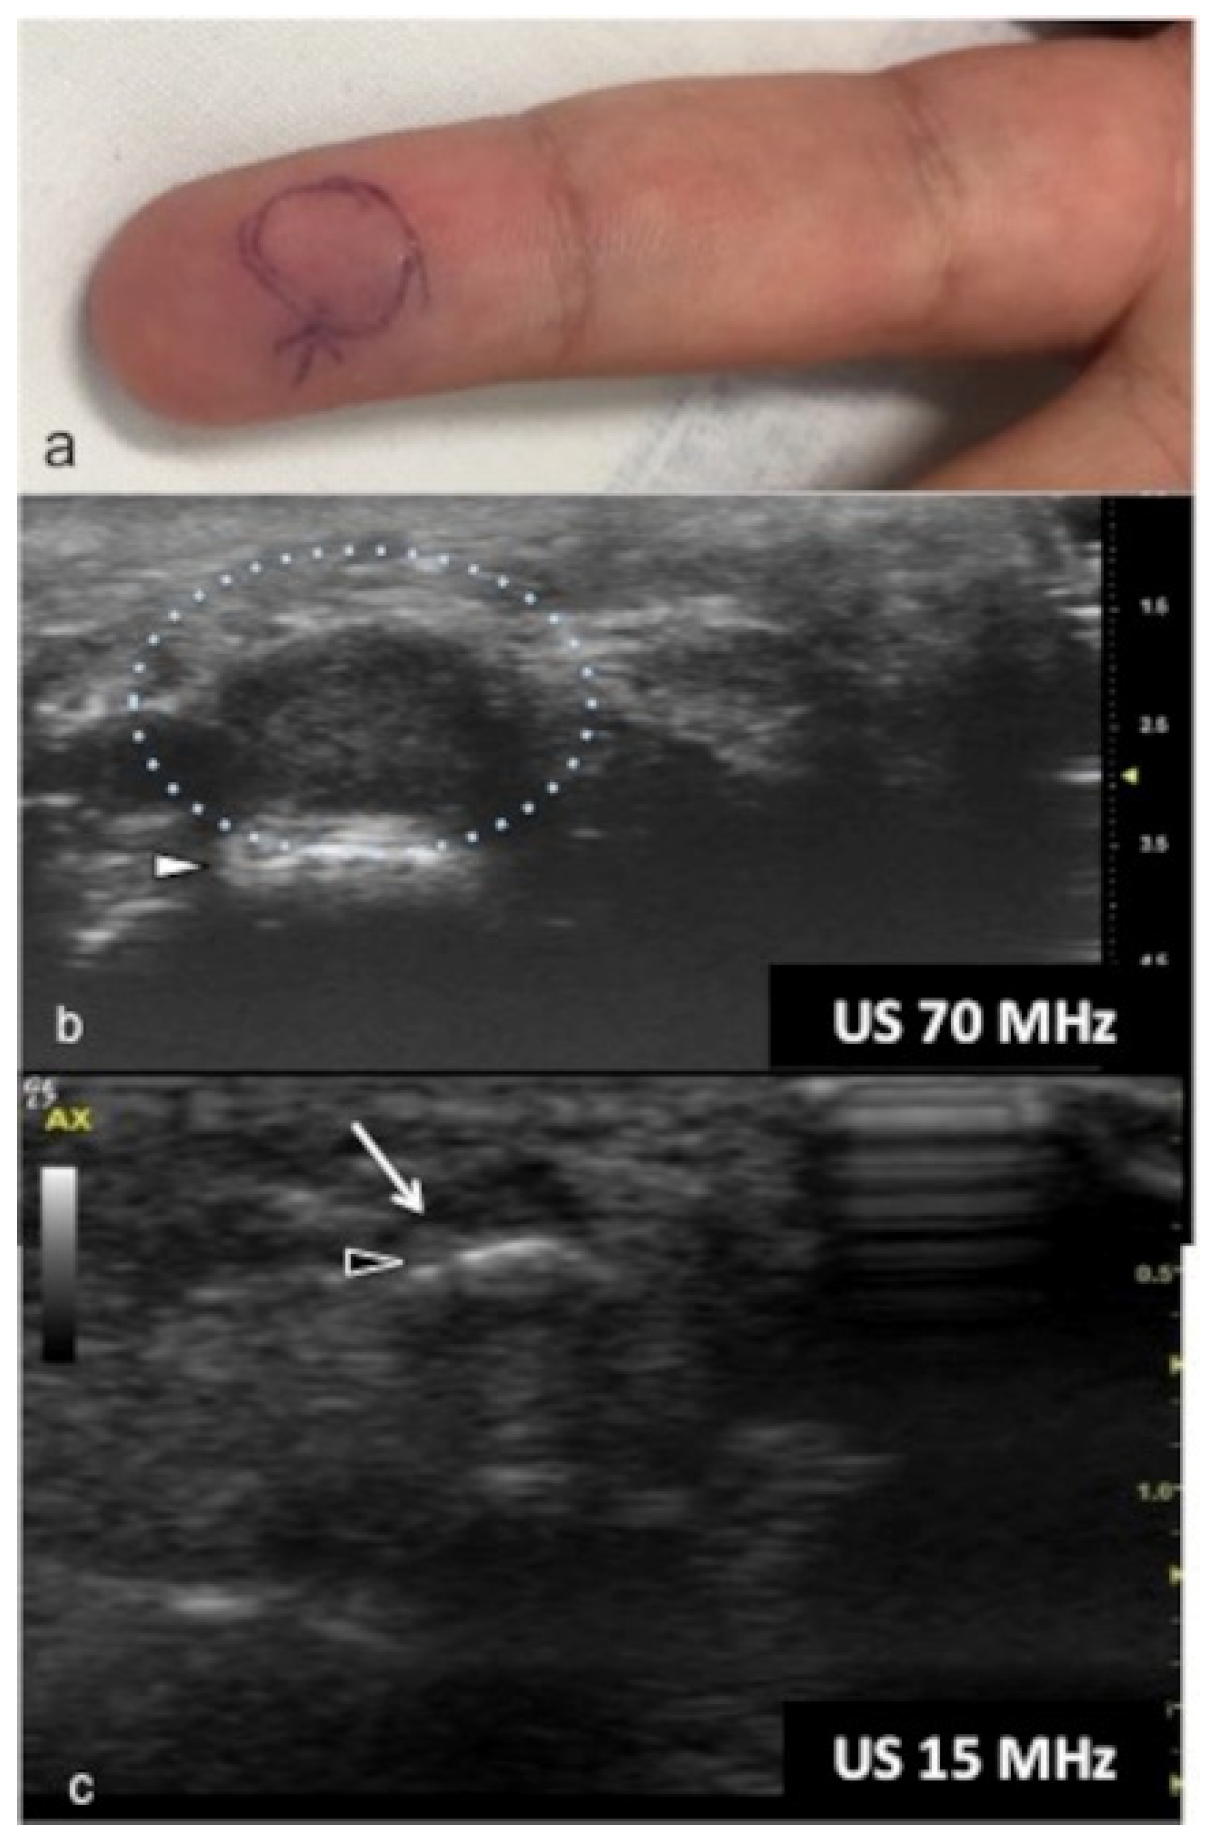

UHFUS could represent an advantageous technique for the identification of small and soft-tissue neoformations such as glomus tumors (Figure 11 and Figure 12).

Figure 11.

Glomus tumor. The location corresponds to the pulp of finger IV (a). The patient had the classical triad of symptoms: paroxysmal pain, pinpoint pain, and cold hypersensitivity, lasting for two years. In (b), UHFUS shows a well-delimited nodule in contact with the adjacent phalangeal bone (arrowhead), but no cortical deformity is present. No significant hyperemia on color Doppler was noticed. On CUS (c), the nodule was delineated only thanks to the help of the preliminary UHFUS exam.

Figure 12.

Glomus tumor in the subungual space. No clear alterations were visible during clinical examination at the site of pain (circle in (a)). In (b), UHFUS effectively demonstrates the presence of a hypo-isoechogenic nodule (calibers) in contact with the adjacent phalangeal bone (arrowhead) under the nail plate (arrows). Note the small deformation of the nail plate. Mild vascularization on color Doppler was present (c).

Glomus tumors are rare, benign, vascular neoplasms arising from the glomus body, which is a contractile neuromyoarterial structure found in the reticular dermis. This structure controls blood pressure and temperature by regulating blood flow in the cutaneous vasculature. Hyperplasia in any of these parts can lead to tumor formation, which is extremely painful. Glomus tumors account for 1–5% of soft-tissue tumors of the hand, and 75% of them are subungual in location. Other less commonly involved sites in the hand are the nail matrix, nail bed, and pulp of the finger. The delay in diagnosing these tumors for many years is a significant problem. It is not uncommon that patients are easily misdiagnosed with conditions such as neuropathic complaints, arthritis, or neuralgia and undergo unsuitable treatment. For these reasons, when the clinical examination is equivocal, noninvasive imaging techniques may be needed to aid in the diagnosis and delineate the anatomy preoperatively. Complete surgical excision of the tumor is the only effective treatment. Incomplete excision is considered the main cause of recurrence. US follow-up and/or intraoperative US may be useful for reducing recurrence and ensuring adequate resection, and the UHFUS tool is promising in this field [56].